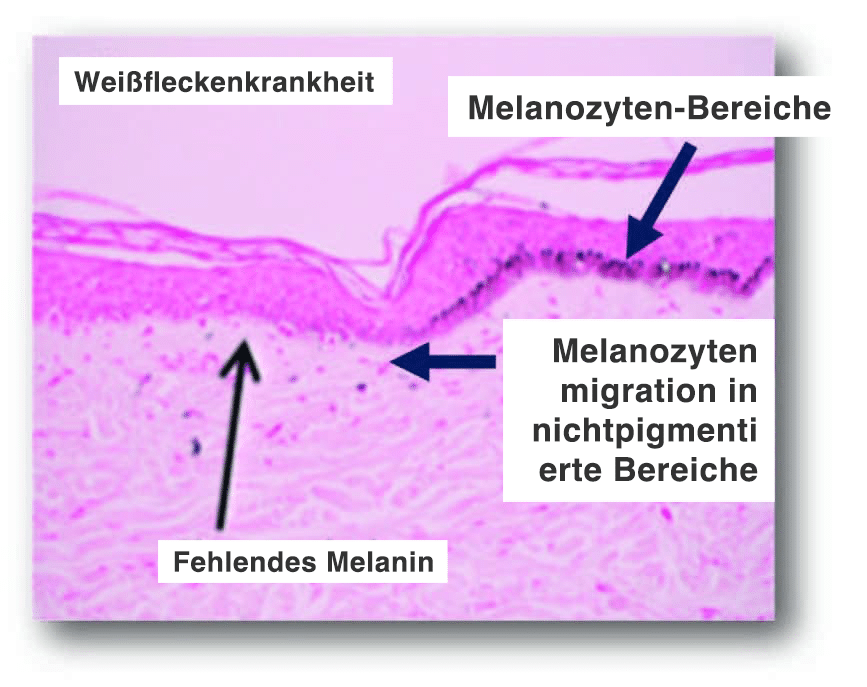

Wirkmechanismus:

- Induzieren der Aktivierung, Migration und/oder Proliferation von Melanozyten in hypopigmentierte Bereiche in der dermal-epidermalen Junktionszone (DEJ). Dieser flache Dermisbereich ist die Zieltiefe.

- Darüber hinaus stimuliert ein mechanisches Trauma die Migration der Melanozyten von den pigmentierten zu den unpigmentierten Bereichen.

- Das Microneedling kann die Anzahl der Pigmentzellen erhöhen und eine höhere Pigmentproduktion stimulieren

Die Mikrokanäle bieten Raum für die Melanozyten, um in nichtpigmentierte Bereiche zu wandern